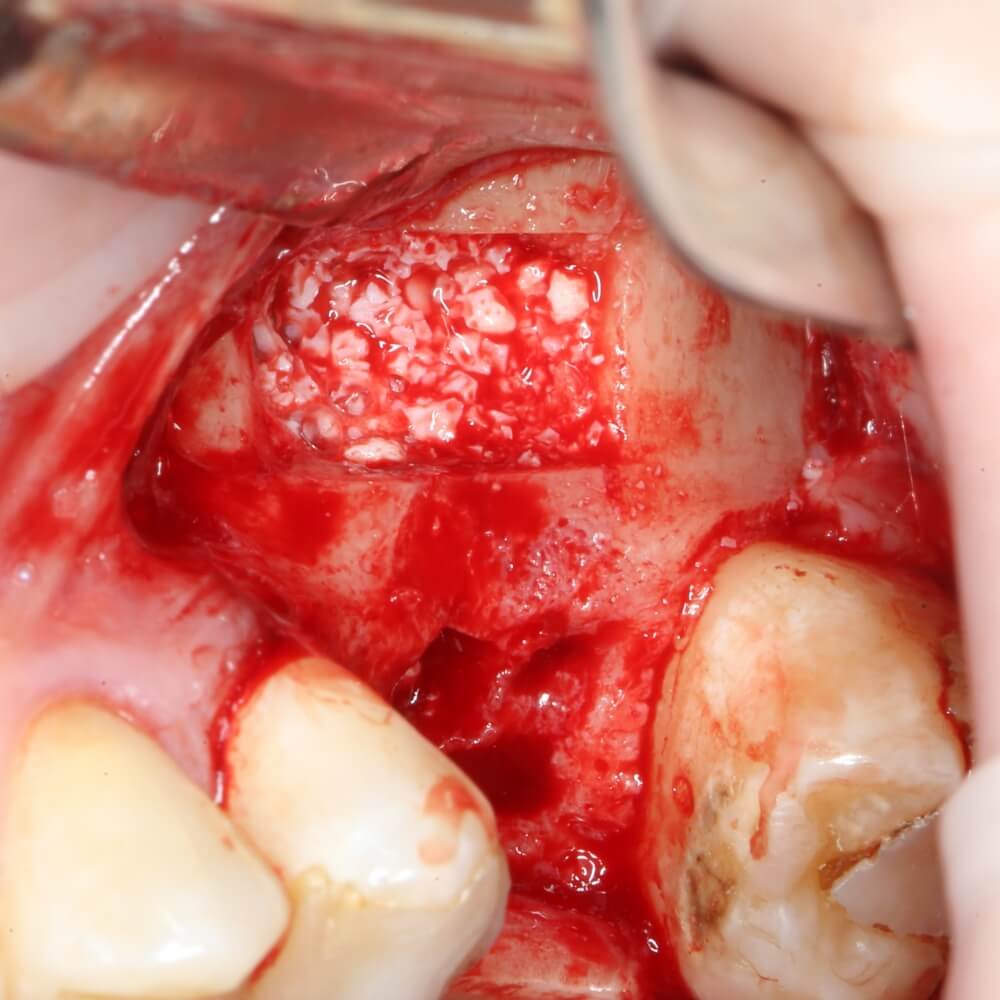

Пришло время вернуться к синуслифтингу и заполнить сформированное ранее субантральное пространство графтом (Geistlich Bio-Oss Pen):

запечатываем заполненное субантральное пространство: